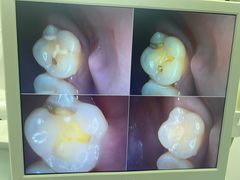

• 牙博士口腔品牌连锁(杨浦店)

• -牙博士口腔品牌连锁(杨浦店)